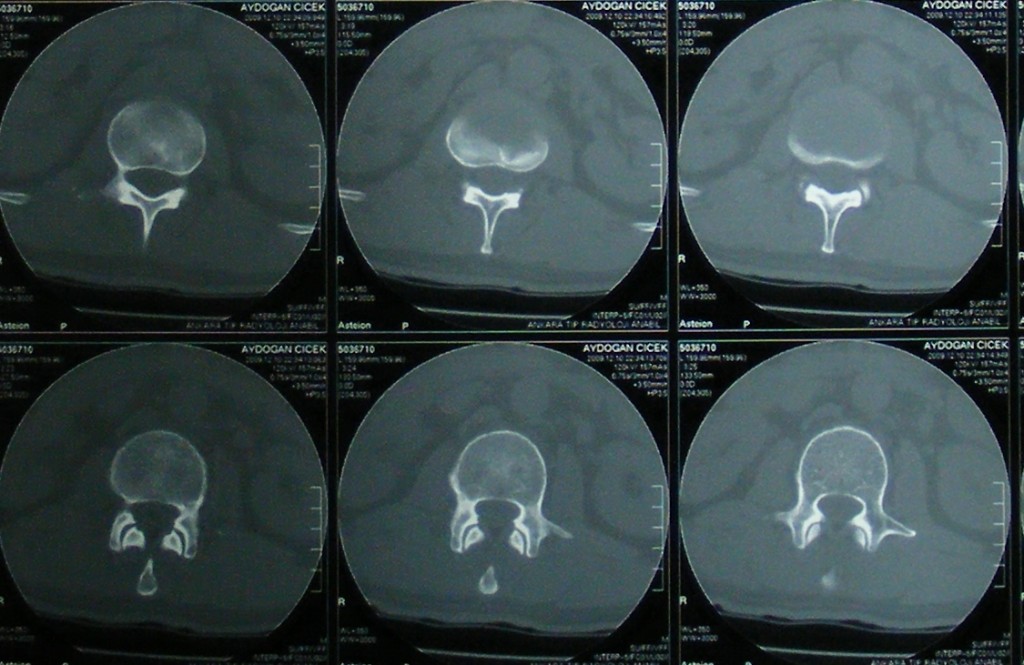

Omurga Kırığı

Omurga kırıkları osteoporozun olmadığı sağlıklı kişilerde trafik kazası ya da yüksekten düşme gibi yüksek enerjili travmalar sonucu oluşur. Eğer omurilik basısına neden olursa kısmi ya da tam felç ile sonuçlanabilir.

Eğer travma ilerleyen dönemde deformiteye yol açmayacaksa veya sinirlere baskı yaparak nörolojik bulguya neden olmadıysa korse ile tedavi edilebilir. Bu amaçla sert polietilen korseler ya da metalden yapılmış çerçeve tipi korseler kullanılabilir. Omurganın ağır zarar gördüğü durumlarda ileride oluşabilecek deformiteyi engellemek için omurganın vida ve çubuklarla sabitlenmesi gerekebilir. Nörolojik bulgu oluşturan bir kemiksel bası varsa, aynı seansta bu bası da ortadan kaldırılabilir.